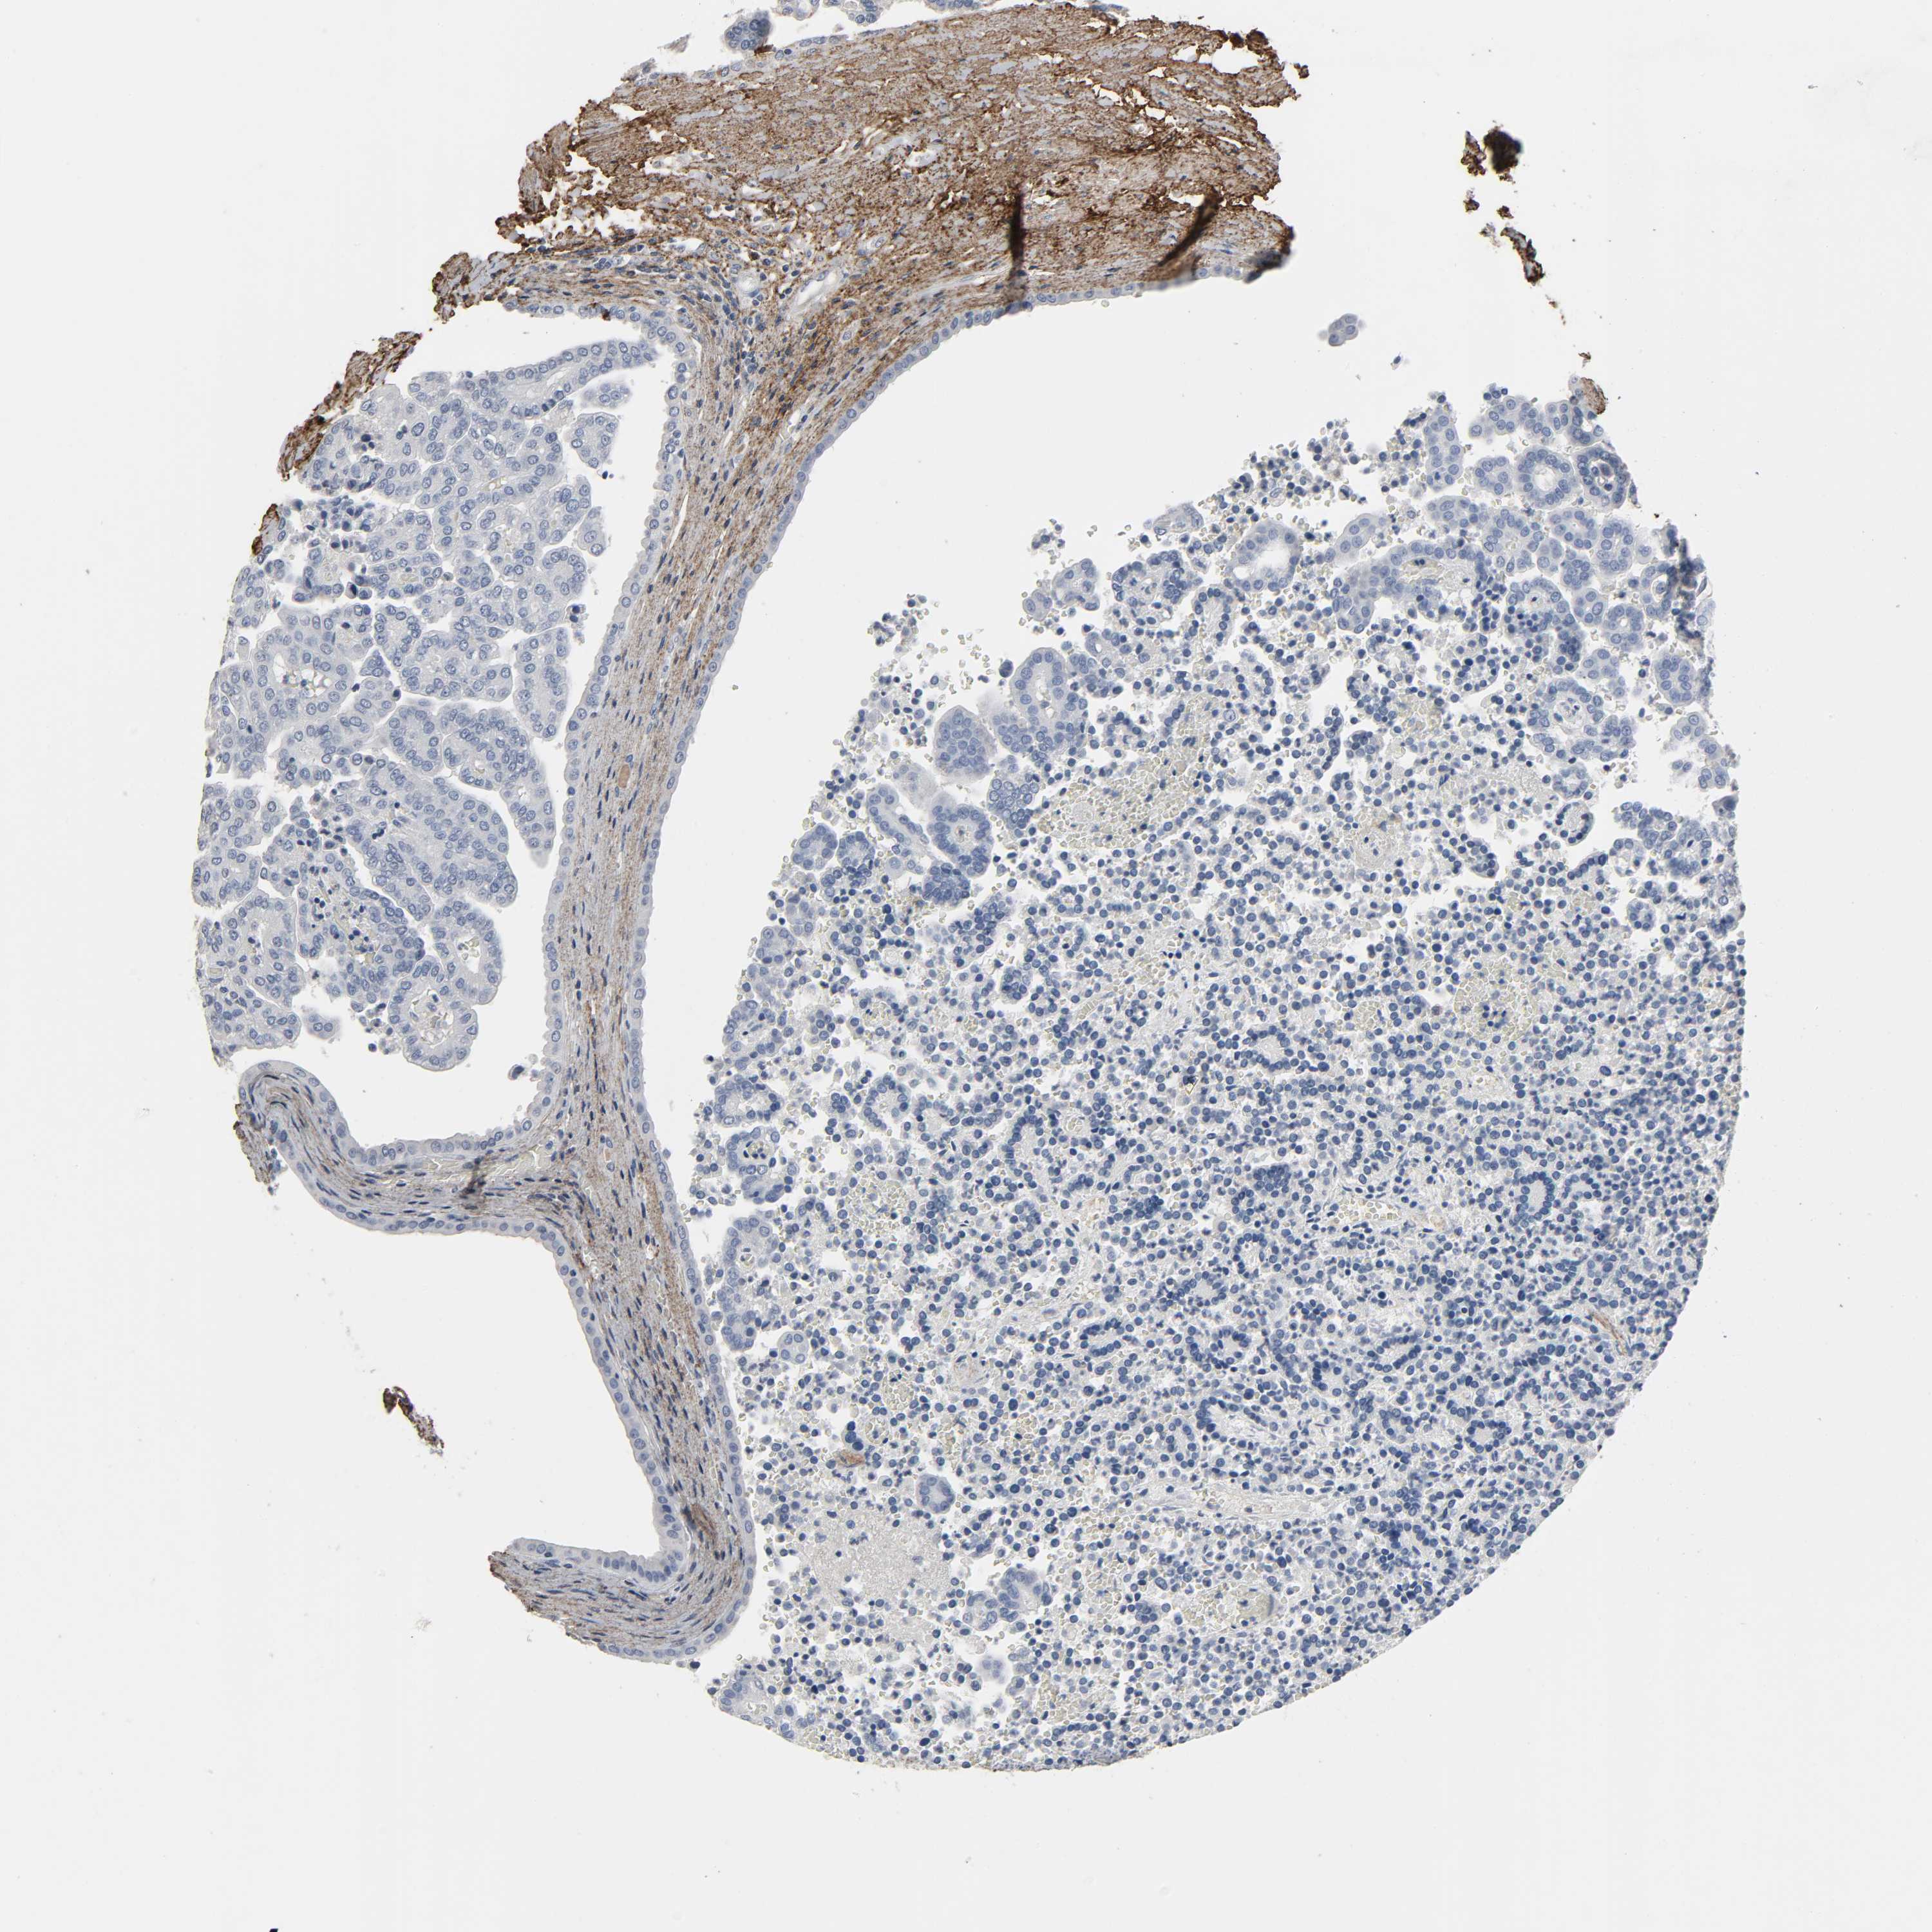

FBLN5